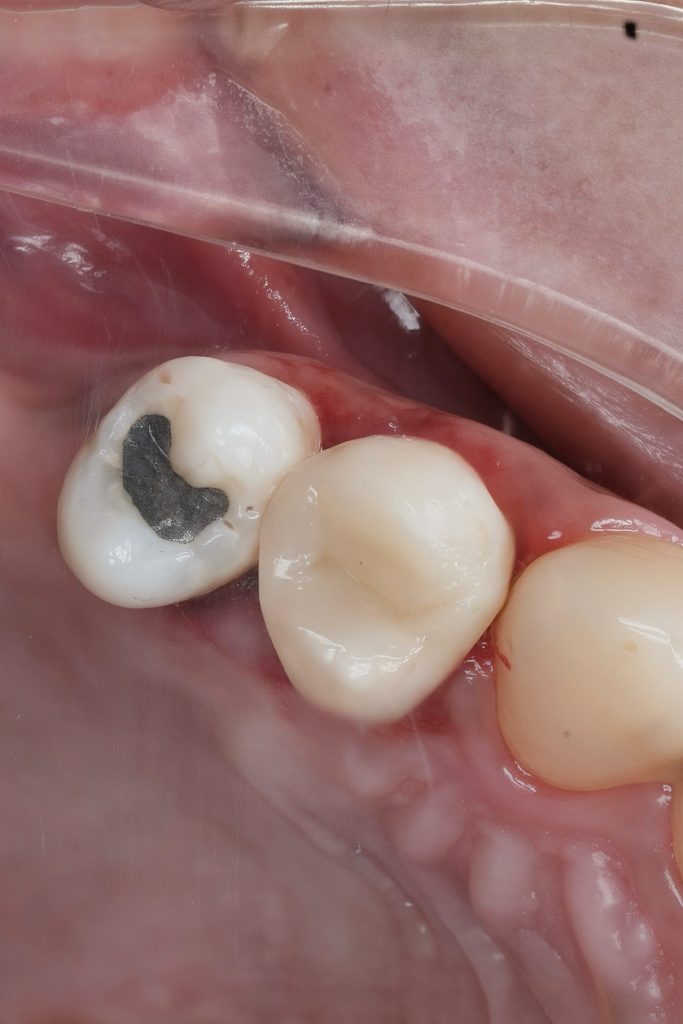

This case demonstrates the complete management of a maxillary premolar with irreversible pulpitis and compromised coronal structure. The treatment involved root canal therapy under rubber dam isolation, followed by adhesive restoration to ensure functional and esthetic rehabilitation.

1. Initial Presentation